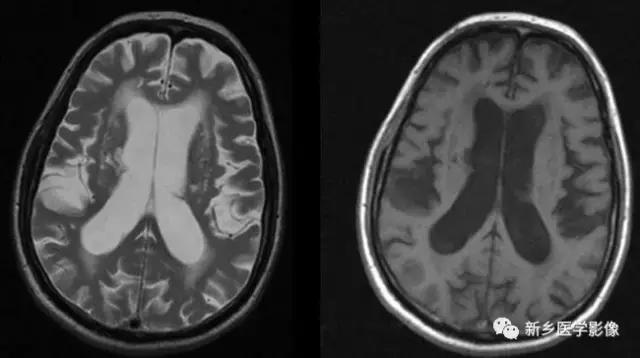

外伤后脑萎缩,感染后脑萎缩,脑梗死后脑萎缩CT可见扩大的脑室部分附近的脑实质呈片状低密度灶MR:T1WI呈低信号,T2WI呈高信号。同时脑沟及蛛网膜下腔增宽。

普遍性脑萎缩常同时累及灰质和白质.可表现有双侧侧脑室扩大。而且是双侧侧脑室轻度对称性扩大最常见的原因。尤其是以脑白质萎缩为主的病人。

普遍性脑萎缩引起的侧脑室扩大通常比较对称.中线无移位。其特点是同时有脑沟、脑裂增宽等脑皮质萎缩的表现.